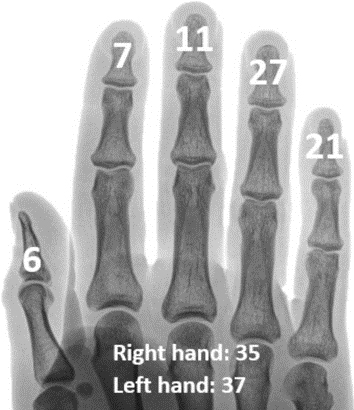

В соответствии с различной степенью отрыва дистального отдела суставов пальцев классификация (рисунок ниже) основана на результатах классификации Wehbé и Schneider: на подтип A приходится 3%, на подтип B — 95,5%, а на подтип C — 1,5%.

Молотчатые пальцы классифицируют на различные типы в зависимости от пораженной суставной поверхности (подтип А: <1/3; подтип В: 1/3-2/3; подтип С: > 2/3) и наличия подвывиха (тип I1: нет Ладонный подвывих, тип II2: ладонный подвывих) и перелом пластинки роста (тип III).

Вероятность появления висячих пальцев на каждом пальце